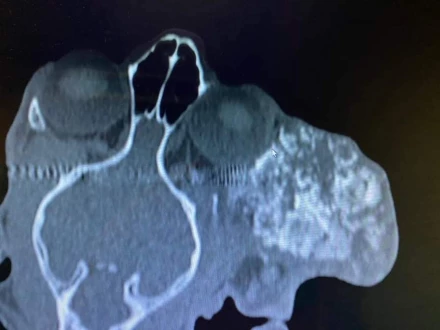

Operacja masywnej zmiany twarzoczaszki